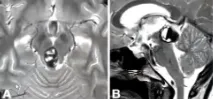

磁共振检查结果很快明确:松果体区存在病变,并发梗塞性脑积水。

女儿爱发呆的表现实为大脑发出的求救信号。情况危急,患儿被迅速推入手术室,必须立即手术以缓解脑积水。实施内镜下第三脑室造瘘术后,关女士才得以暂时松一口气。

松果体为位于大脑中心的红灰色小腺体,大小仅约5-8毫米,却可能发生超过17种不同类型的病变。其解剖位置深在,位于上丘脑,处于两侧大脑半球之间,藏于丘脑连接处的沟槽内,毗邻第三脑室、胼胝体、丘脑等重要结构及关键血管,手术难度极高。

巴教授采用幕下小脑上入路,成功暴露病变区域。术中发现病变为典型的海绵状血管瘤,并伴有新鲜的病灶内出血。最终,巴教授成功将血管瘤完整切除,术中未造成任何并发症。